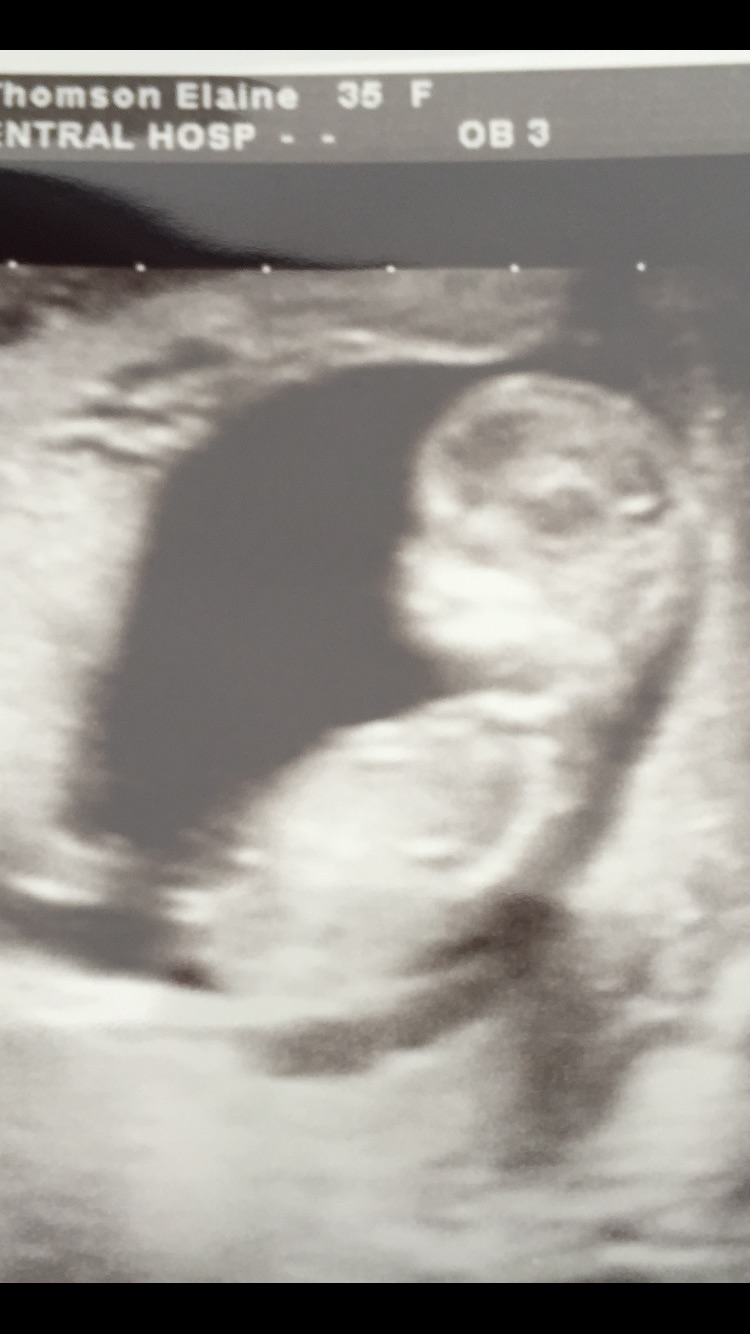

Hey I just wondered if it's clear from 12 week scan pic that it's a girl? I'm clueless!!Attachment 24206

I'm thinking that's nub showing but unsure!! Any experts or people with knowledge!! Thank you!!

It's forked like a girl...the angle looks weird because of the pitcure and position of baby but the Harmony test says girl. It's a girl.

If Harmony says it's a girl, it's a girl. Agree not the best pic for guessing but very cute little bug!

Forked , girly skull. bad angle so you may have had a few boy guesses but that's a girl Harmony is super accurate nub guessing is not!! Xxx